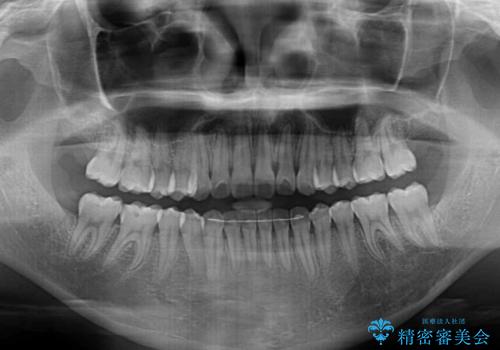

オープンバイトでかみにくい インビザラインによる矯正治療

- 前歯の上下スペースによる食べにくさを気にして来院された患者様です。

インビザラインにより上下の前歯の隙間を閉じていくこととしました。

上下の奥歯を圧下させるようにすることで、前歯を接触させるように計画しました。

上下の隙間に舌が入り込むことがオープンバイトの原因であったため、舌の筋肉のトレーニングも並行して行い、後戻りの抑制を図りました。